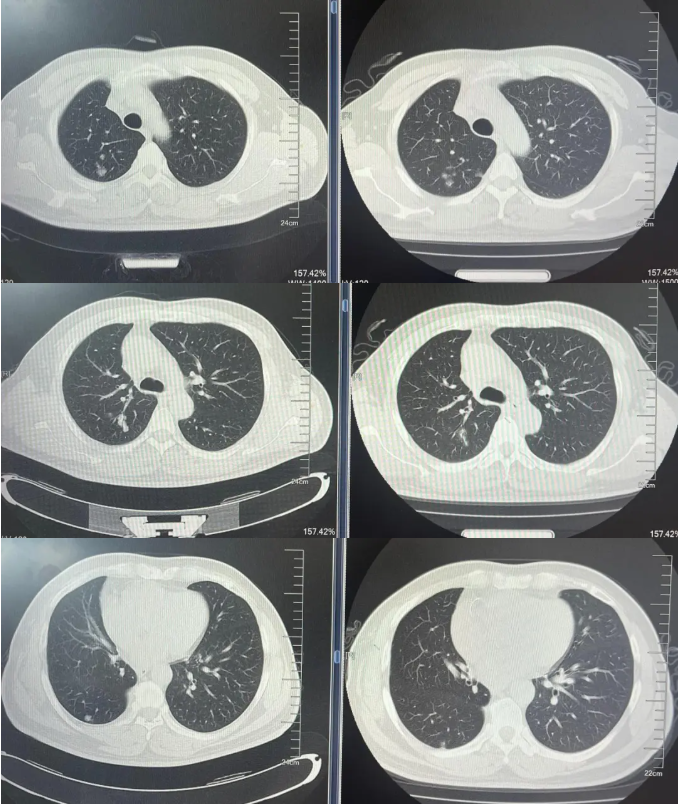

病例1:患者男,68岁。2024年6月以“胸闷气短1个月”为主诉于当地医院检查治疗。查CT提示左肺下叶肿物,纵隔、双肺门多发肿大淋巴结,左侧胸腔积液,左侧胸膜增厚。于当地医院行胸水穿刺引流查癌细胞提示肺腺癌。临床分期:cT2aN3M1a IVA期。患者于当地医院行血液基因检测未见敏感突变,使用AP方案化疗后病情进展。2025-1入我院后行肺穿刺活检,病例提示腺癌。行基因检测提示:ERBB2突变(丰度3.5%)。行德曲妥珠单抗(T-DXd)治疗至今。最佳疗效PR,目前持续有效中,PFS已超过7个月。患者使用德曲妥珠单抗期间出现II级恶心呕吐,经对症治疗可缓解。

德曲妥珠单抗治疗4周期(2025.5)疗效对比

德曲妥珠单抗治疗6周期(2025.7)疗效对比

病例1治疗经过

病例2:患者男,61岁。2023年8月于外院行肺CT提示:右肺下叶肿块。2023年10月23日于我院行单孔胸腔镜下右肺下叶切除术、肺门纵隔淋巴结扩清术。术后病理:腺癌低分化(腺泡型占30%,乳头型占30%,筛状占30%,微乳头占10%)。分期pT4N0M0 IIIA期。术后行基因检测提示HER2+(14%),PD-L1 2%+。术后行AC方案化疗4周期后行阿替利珠单抗维持治疗1年。末次用药时间:2024年11月1日。2025年2月复查肿瘤标志物升高,肺HRCT示:双肺多发结节,考虑转移。行血液基因检测提示:ERBB2 35.5%突变,CDK1 9.5%突变,MDM2 4.92%突变。患者DFS 14m,阿替利珠单抗停药后3个月出现复发转移,可见传统免疫治疗效果不佳。恰逢德曲妥珠单抗一线新尝试DESTINY-lung 04研究公布了入组标准和治疗方案,且该患在术后的组织基因检测和复发后的血液基因检测中都明确存在HER2突变,故行德曲妥珠单抗一线治疗。最佳疗效PR,目前治疗持续有效,PFS超过6个月。无药物相关不良反应发生。

德曲妥珠单抗治疗4周期(2025.4)疗效对比

病例2治疗经过